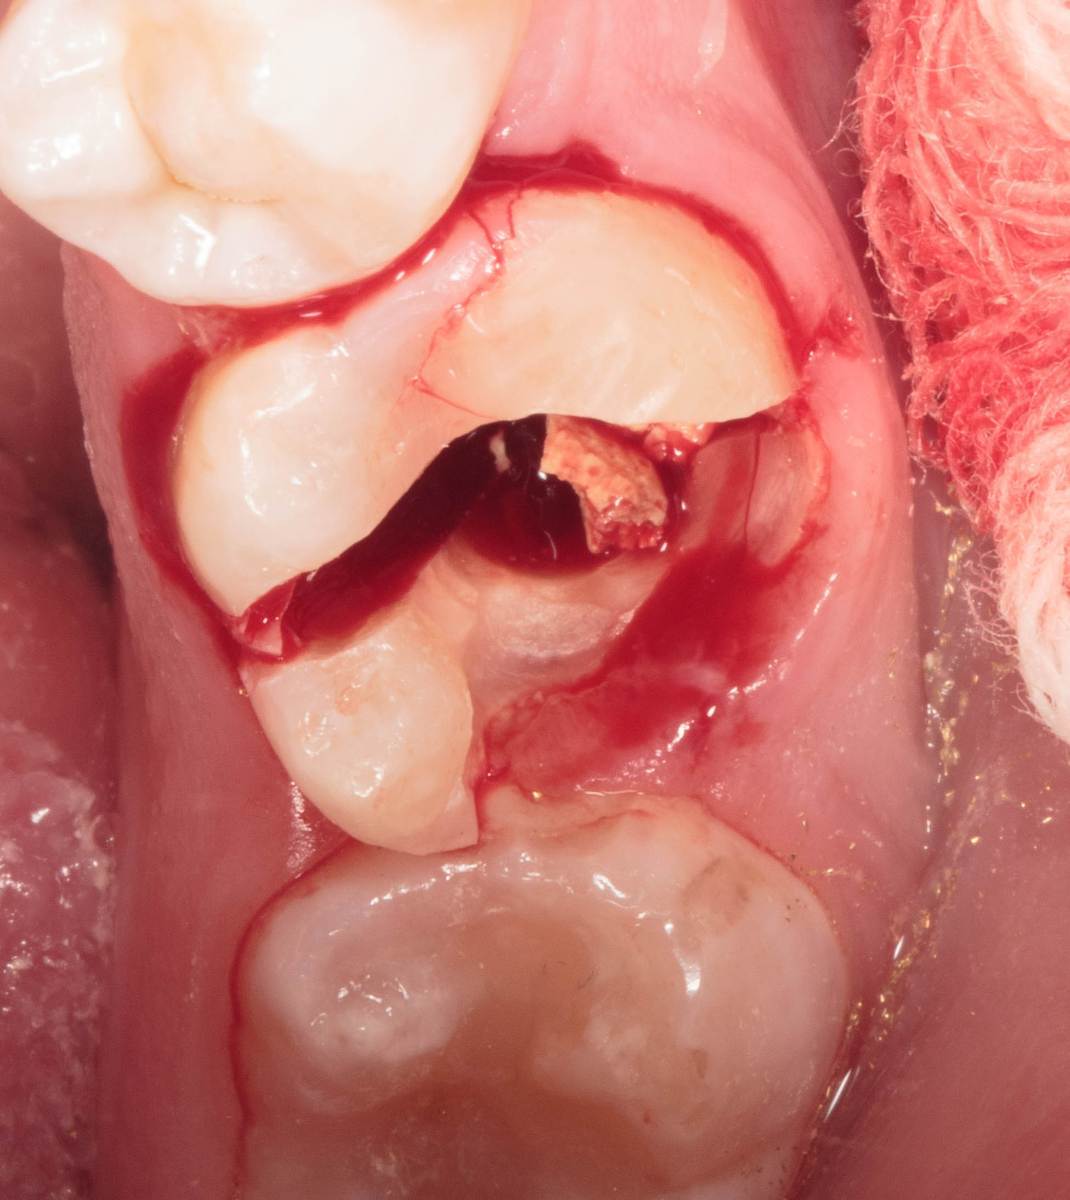

Женька Опубликовано 28 ноября, 2025 Поделиться Опубликовано 28 ноября, 2025 Всем привет, коллеги! 14 лет, терапевты ставят трещину по КТ (снимков до, к сожалению нет, косяк, каюсь). чуть сепарировав зуб и глянув на зуб под отлетевшим куском пломбы трещина "подтвердилась". Кейс на фото. Из интересного - маленький реколл в 1.5 года и спокойное перемещение зуба брекетами! 4 1 2 Ссылка на комментарий